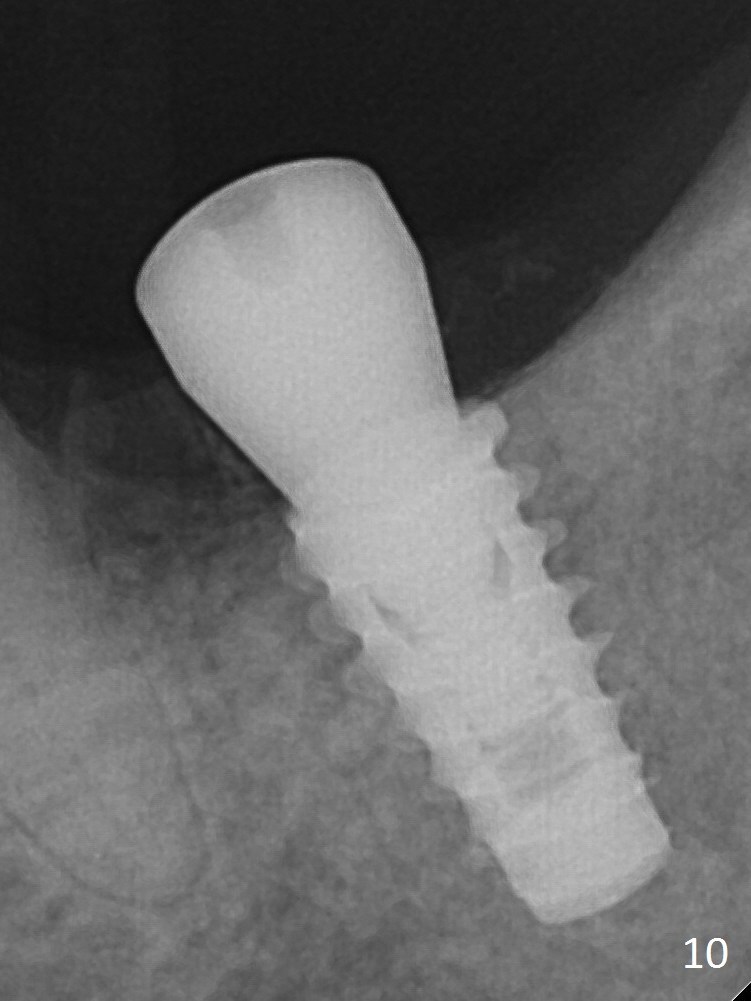

There is chewing pain in spite of previous occlusal adjustment 7 months post cementation (Fig.11-13: increased radiolucency around the implant). The crown/abutment is removed and a healing abutment is placed (6x3 mm); the implant is found to be stable. The patient will return for re-evaluation in 3 months. Check proximal contact after crown reseating. Occlusion should be light, since #18 is the only molar with a natural opposing tooth (heavy occlusion). The patient return for re-evaluation in 3 months (15 months postop); radiolucency appears to reduce (Fig.14). But there is pain when the healing abutment is being removed. After local anesthesia, the implant is removed with a wrench.